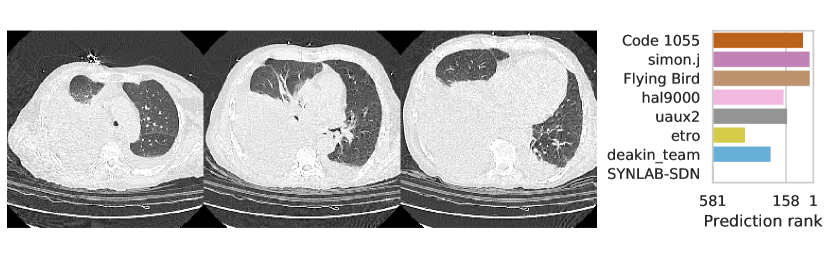

3.2.3 Performance

Table 1 shows the AUC on test set B for COVID-19 presence and severity of the teams that submitted to the Final phase. Figure 4 shows Receiving Operating Characteristics (ROC) curves of the six successful Final phase submissions for discriminating between severe and non-severe COVID-19 subjects from test set B. Figures 5 and 6 show how the finalists ranked the subjects from test set B with severe and non-severe COVID-19 respectively for presence of severe COVID-19. Figures 7 and 8 highlight some individual cases from test set B. During the original STOIC project [67], a logistic regression model was developed to predict severe COVID-19 using clinical variables and CT annotations by radiologists. It was developed and evaluated using the patients from the STOIC who were COVID-19 positive for both RT-PCR and CT, and had unenhanced CT. Of these 4238 patients, 1000 developed severe COVID-19. Revel and colleagues 6 reported an AUC for this model of 0.69 (CI: 0.67-0.71). To compare this model against the results from STOIC2021, an ensemble of the top three solutions for severe COVID-19 prediction was evaluated on the 367 patients from test set B who were COVID-19 positive for both RT-PCR and CT, and had unenhanced CT. 97 of these patients developed severe COVID-19. The top three ensemble achieved an AUC of 0.783 (CI: 0.706-0.848).